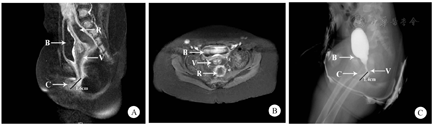

患儿口服水合氯醛镇静后取仰卧位,使用1.5-T磁体线圈腹部序列对下腹部及盆区进行薄层扫描。T2矢状面序列加做脂肪抑制序列扫描。测量矢状位片阴道与小阴唇之间的直线距离(图2A中黑色线段)或水平面共同通道层数(图2B)作为共同通道长度用于手术决策。

注:B,膀胱;R,直肠;C,共同通道;V,阴道;黑色线段,指示共同通道长度

经共同通道置入6F/8F硅胶尿管,透视下注入水溶性造影剂。与共同通道相连的盆腔管道结构显影后行正、侧位X线摄片。考虑存在合并泌尿系统畸形者,经共同通道插管入膀胱后行逆行膀胱尿路造影术,测量阴道与小阴唇间的直线距离(图2C中黑色线段)作为共同通道长度用于手术决策。

二次评估主要围绕为根治手术术式选择提供可靠依据而展开。超声经济、无辐射,无需镇静,为两次评估最常用的检查手段,本研究有29例(93.55%)采用超声评估泌尿生殖系统畸形。泄殖腔造影检查是传统的评估手段,虽有成功率低、存在射线辐射等缺点,但其对各腔道形态和功能的动态显示作用仍不可替代,目前旋转透视三维重建等方法让立体评估成为可能[11]。MR对盆腔组织器官分辨率高,是泄殖腔畸形术前评估的理想手段[12,13,14]。然而是否应在首次评估(新生儿期)完善MR检查尚存在争议。欧洲儿科放射学学会认为MR产生噪音且需深度镇静,在中枢神经系统、泌尿生殖系统的评估作用并非不可替代,故不推荐直肠肛门畸形患儿新生儿期常规行MRI检查[15]。本组有12例(38.71%)在新生儿期行MR检查,2次评估共27例(87.10%)行MR。最重要的一步即通过测量共同通道长度确定泄殖腔畸形分型,后者直接决定了手术的入路和阴道替代的方式。本研究主要采用MR、共同通道造影及内窥镜3种方式,其原则均相同,即测量从可识别的阴道末端到会阴(小阴唇)的直线距离。如阴道因闭锁、缺如等原因不可见,则测量直肠末端到会阴的距离作为共同通道的长度。采用这种测量方法的原因如下:首先,阴道位置为重建手术方式的选择提供了重要信息。术中共同通道一般均卷管后作为尿道保留,直肠拖下肛门成形也可通过充分游离直肠、乙状结肠系膜达成,而阴道位置变化较多,重建术前需要进行详细的检查和计划。其次,在大多数情况下,阴道开口不高于直肠盲端。上述方法可简化问题。有经验的影像科医生与外科医生共同实施检查、阅片,有助于成功辨别共同通道及长度测量。而内窥镜检查能够进一步准确的核实影像学评估、更为立体的呈现泄殖腔畸形的解剖结构,作用同样重要。根据测量结果本组患儿被分为Ⅰ型泄殖腔畸形、低位畸形及高位畸形三型,分别对应阴道后壁下移、尿生殖窦整体下移及阴道替代手术3种手术方式,术中所见均证实了这种分型依据的准确性。